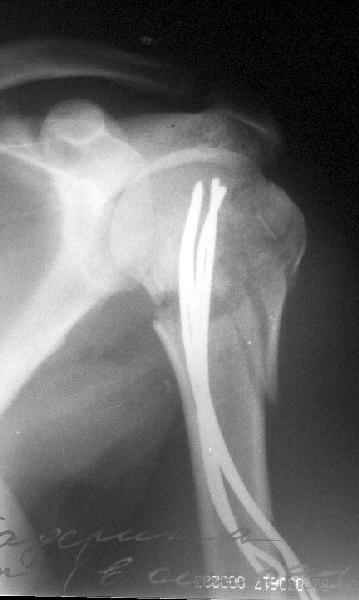

Здесь случай перелома-вывиха плеча, больному 56 лет, после "дважды" закрытой неудачной репозиции, опять же ургентно взяли в операционную, после полного общего обезболивания попытались сделать репозицию, и фиксацию провели спицами.

Больной находился в повязке, примерно напоминяющей косыночную, рекомендованы движения в локтевом суставе и маятниковые движения в плече, спицы удалены в три недели (были случаи миграции)

Больной амбулаторный, предупрежден на случай осложнения АВН головки.